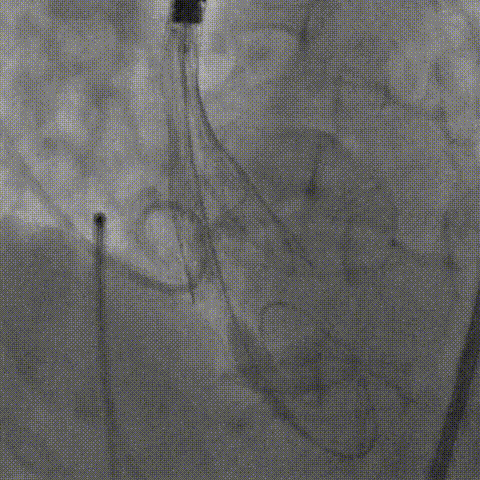

18mm球囊预扩,左冠显影良好

第一次释放,人工瓣膜受自体瓣膜挤压导致下滑

术中,人工瓣膜部分释放时,由于受自体瓣膜的挤压导致人工瓣膜下滑,陶主任立即对人工瓣膜进行了回收再定位,到达预期位置后精准释放,手术结果令人满意。